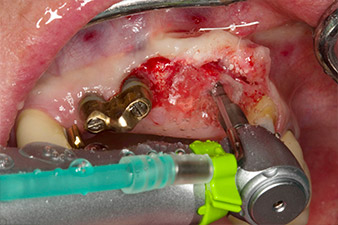

Une fois la cicatrisation primaire obtenue, les tissus mous ont été formés à l'aide du bridge doublé à la base. Deux mois plus tard, la zone a été exposée au moyen d'une incision de la crête alvéolaire légèrement orientée côté palatin (Fig 2). Les dimensions de l'os alvéolaire se sont avérées suffisantes en position 22. Les Figures 2 et 4 illustrent la préparation du lit implantaire, le taraudage et la pose de l'implant à l'aide de l'Implantmed.